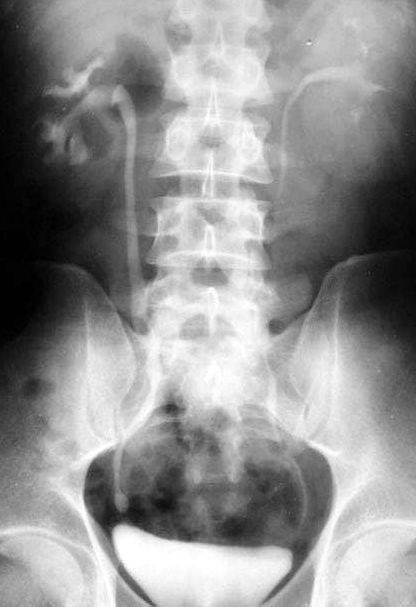

照片名称:膀胱癌5

照片名称:膀胱癌

照片名称:膀胱癌2

照片名称:膀胱癌4